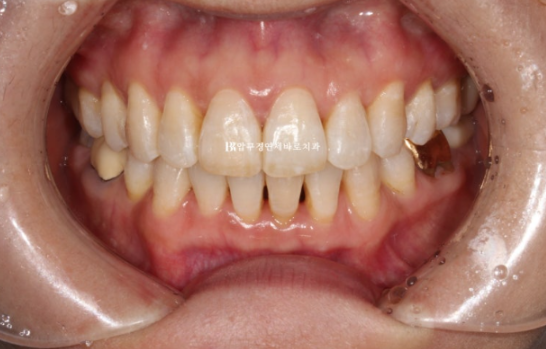

이 정도도 충분히 좋지만 100점 목표를 위해 추가장치 제작을 합니다.

추가장치를 2월부터 5월까지 3달간 10일씩 꼈고 마무리 했습니다.

24.05

위 앞니 블랙트라이앵글은 치간삭제를 통해 줄었으나 삐뚤했던 아래 앞니가 가지런해지면서 블랙트라이앵글이 생겼습니다. 아래도 마찬가지로 치간삭제를 통해 블랙트라이앵글 사이즈를 줄였지만 치간삭제는 치아에 무리가지 않는 선에서 하는 것이 좋습니다.

걱정하시는 교합도 좋습니다.